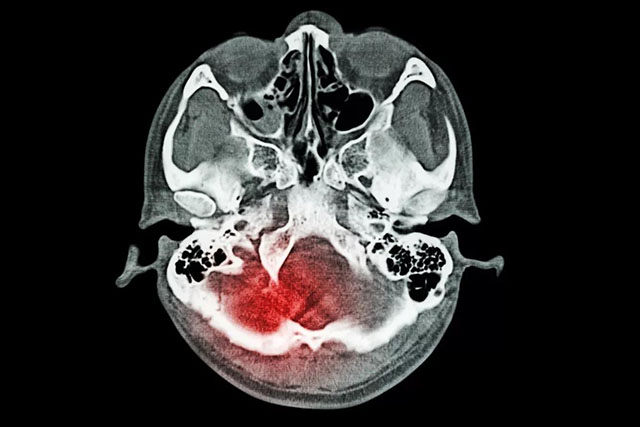

蛛网膜下腔出血是出血性脑血管病的一种,这种疾病和普通的脑出血是不一样的,普通的脑出血一般都是指脑实质内出血,而蛛网膜下腔出血,它是由于脑子里面出血,年轻患者蛛网膜下腔出血大多数都是因为颅内动脉瘤或者脑血管畸形,而老年人患这种疾病一般为动脉瘤脑动脉硬化,这种疾病的病情变化非常快,病情很危重,所以一旦出现头痛的话,可能就会对患者出现昏迷等各种的不良反应影响,严重的话,可能会危及生命。

蛛网膜下腔出血是一种症状表现,由于多种原因引起的脑血管突然破裂,是血液进入颅内或椎管内的蛛网膜下腔所引起的综合征。临床上将蛛网膜下腔出血分为自发性和外伤性两类。

蛛网膜下腔出血的治疗是一项综合治疗,目的是为了防止再出血、血管痉挛及脑积水等并发症,降低死亡率和致残率。在确诊之后,应尽早进行脑血管造影或CT血管成像检查,一旦正式为颅内动脉瘤破裂,尽快准备实施开颅夹闭手术或血管内介入栓塞治疗。